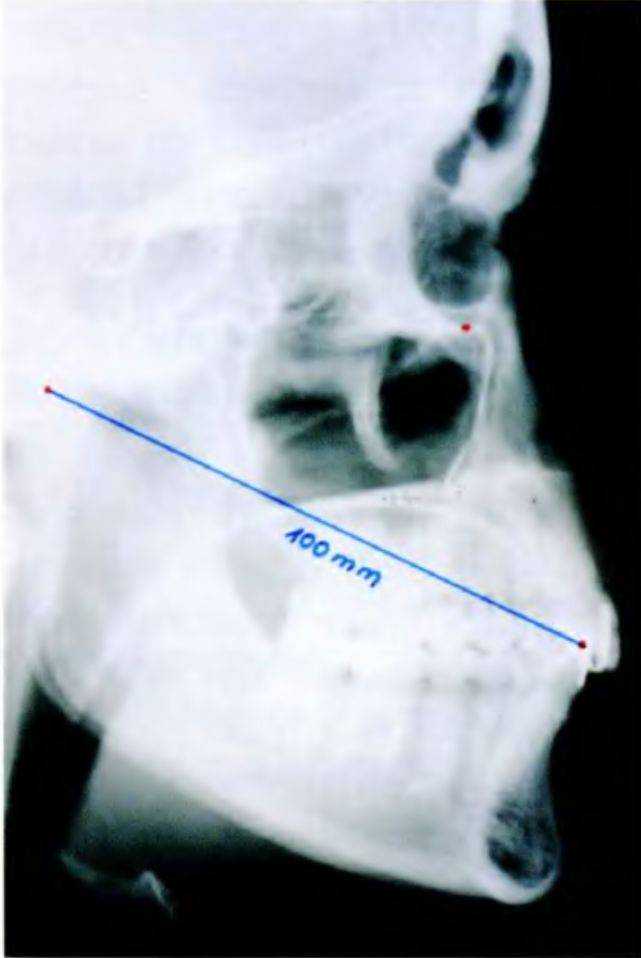

Расстояние от передней точки между центральными резцами до головки нижней челюсти составляет 100 мм (рис. 6-45д).

Рис. 6-45д. Среднее расстояние 100 мм на рентгенограмме

Рис. 6-45f. Средние расстояния между суставной шарнирной осью и режущим краем нижнего центрального резца